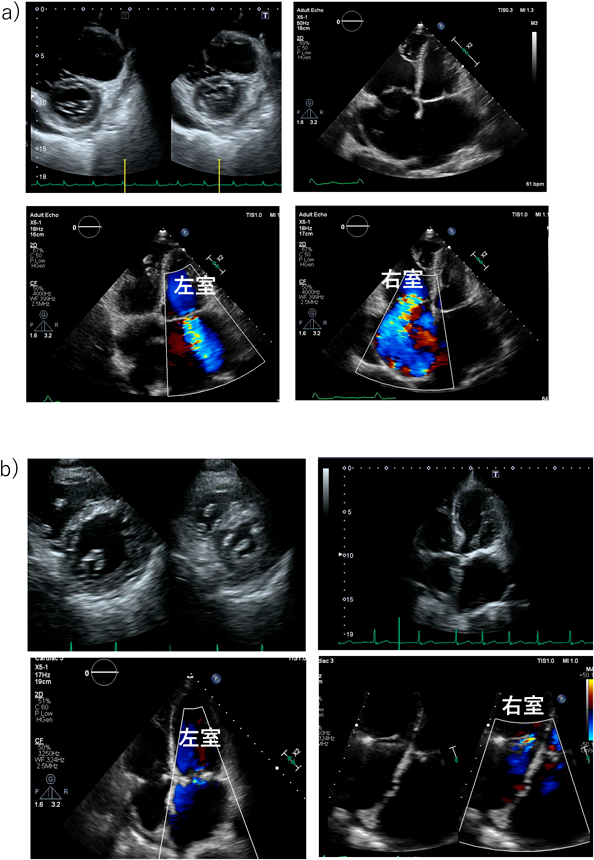

Fig. 2 三尖弁逆流と僧帽弁逆流を合併した79歳ASD患者の心エコー

a)術前には著明な右房,右室拡大,左房拡大を認め,重度三尖弁逆流,中等度僧帽弁逆流を認めた.b)外科的ASD閉鎖+三尖弁形成術+僧帽弁形成術+左心耳閉鎖術後を施行.2年後には弁逆流は制御されており,右心系は縮小した.

Fig. 3 70歳男性の経カテーテル心房中隔欠損症閉鎖術前後での三尖弁逆流の変化

a)心房中隔欠損症閉鎖術前では右心系の拡大に伴う三尖弁輪の拡大と重度の三尖弁逆流を認めた.b)カテーテル閉鎖後2か月ですでに三尖弁逆流は軽度まで改善している.c)カテーテル閉鎖後1年でも三尖弁逆流ごく軽度にとどまっている.